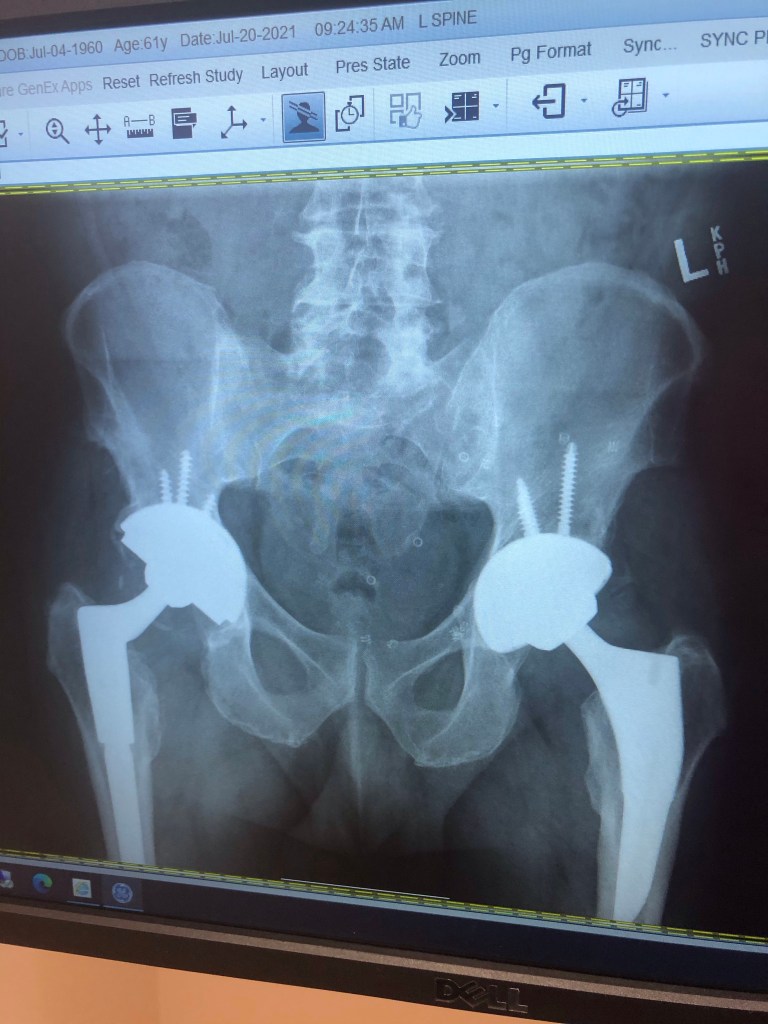

How is it possible for a drivers license renewal to be more complicated than my hip replacement?